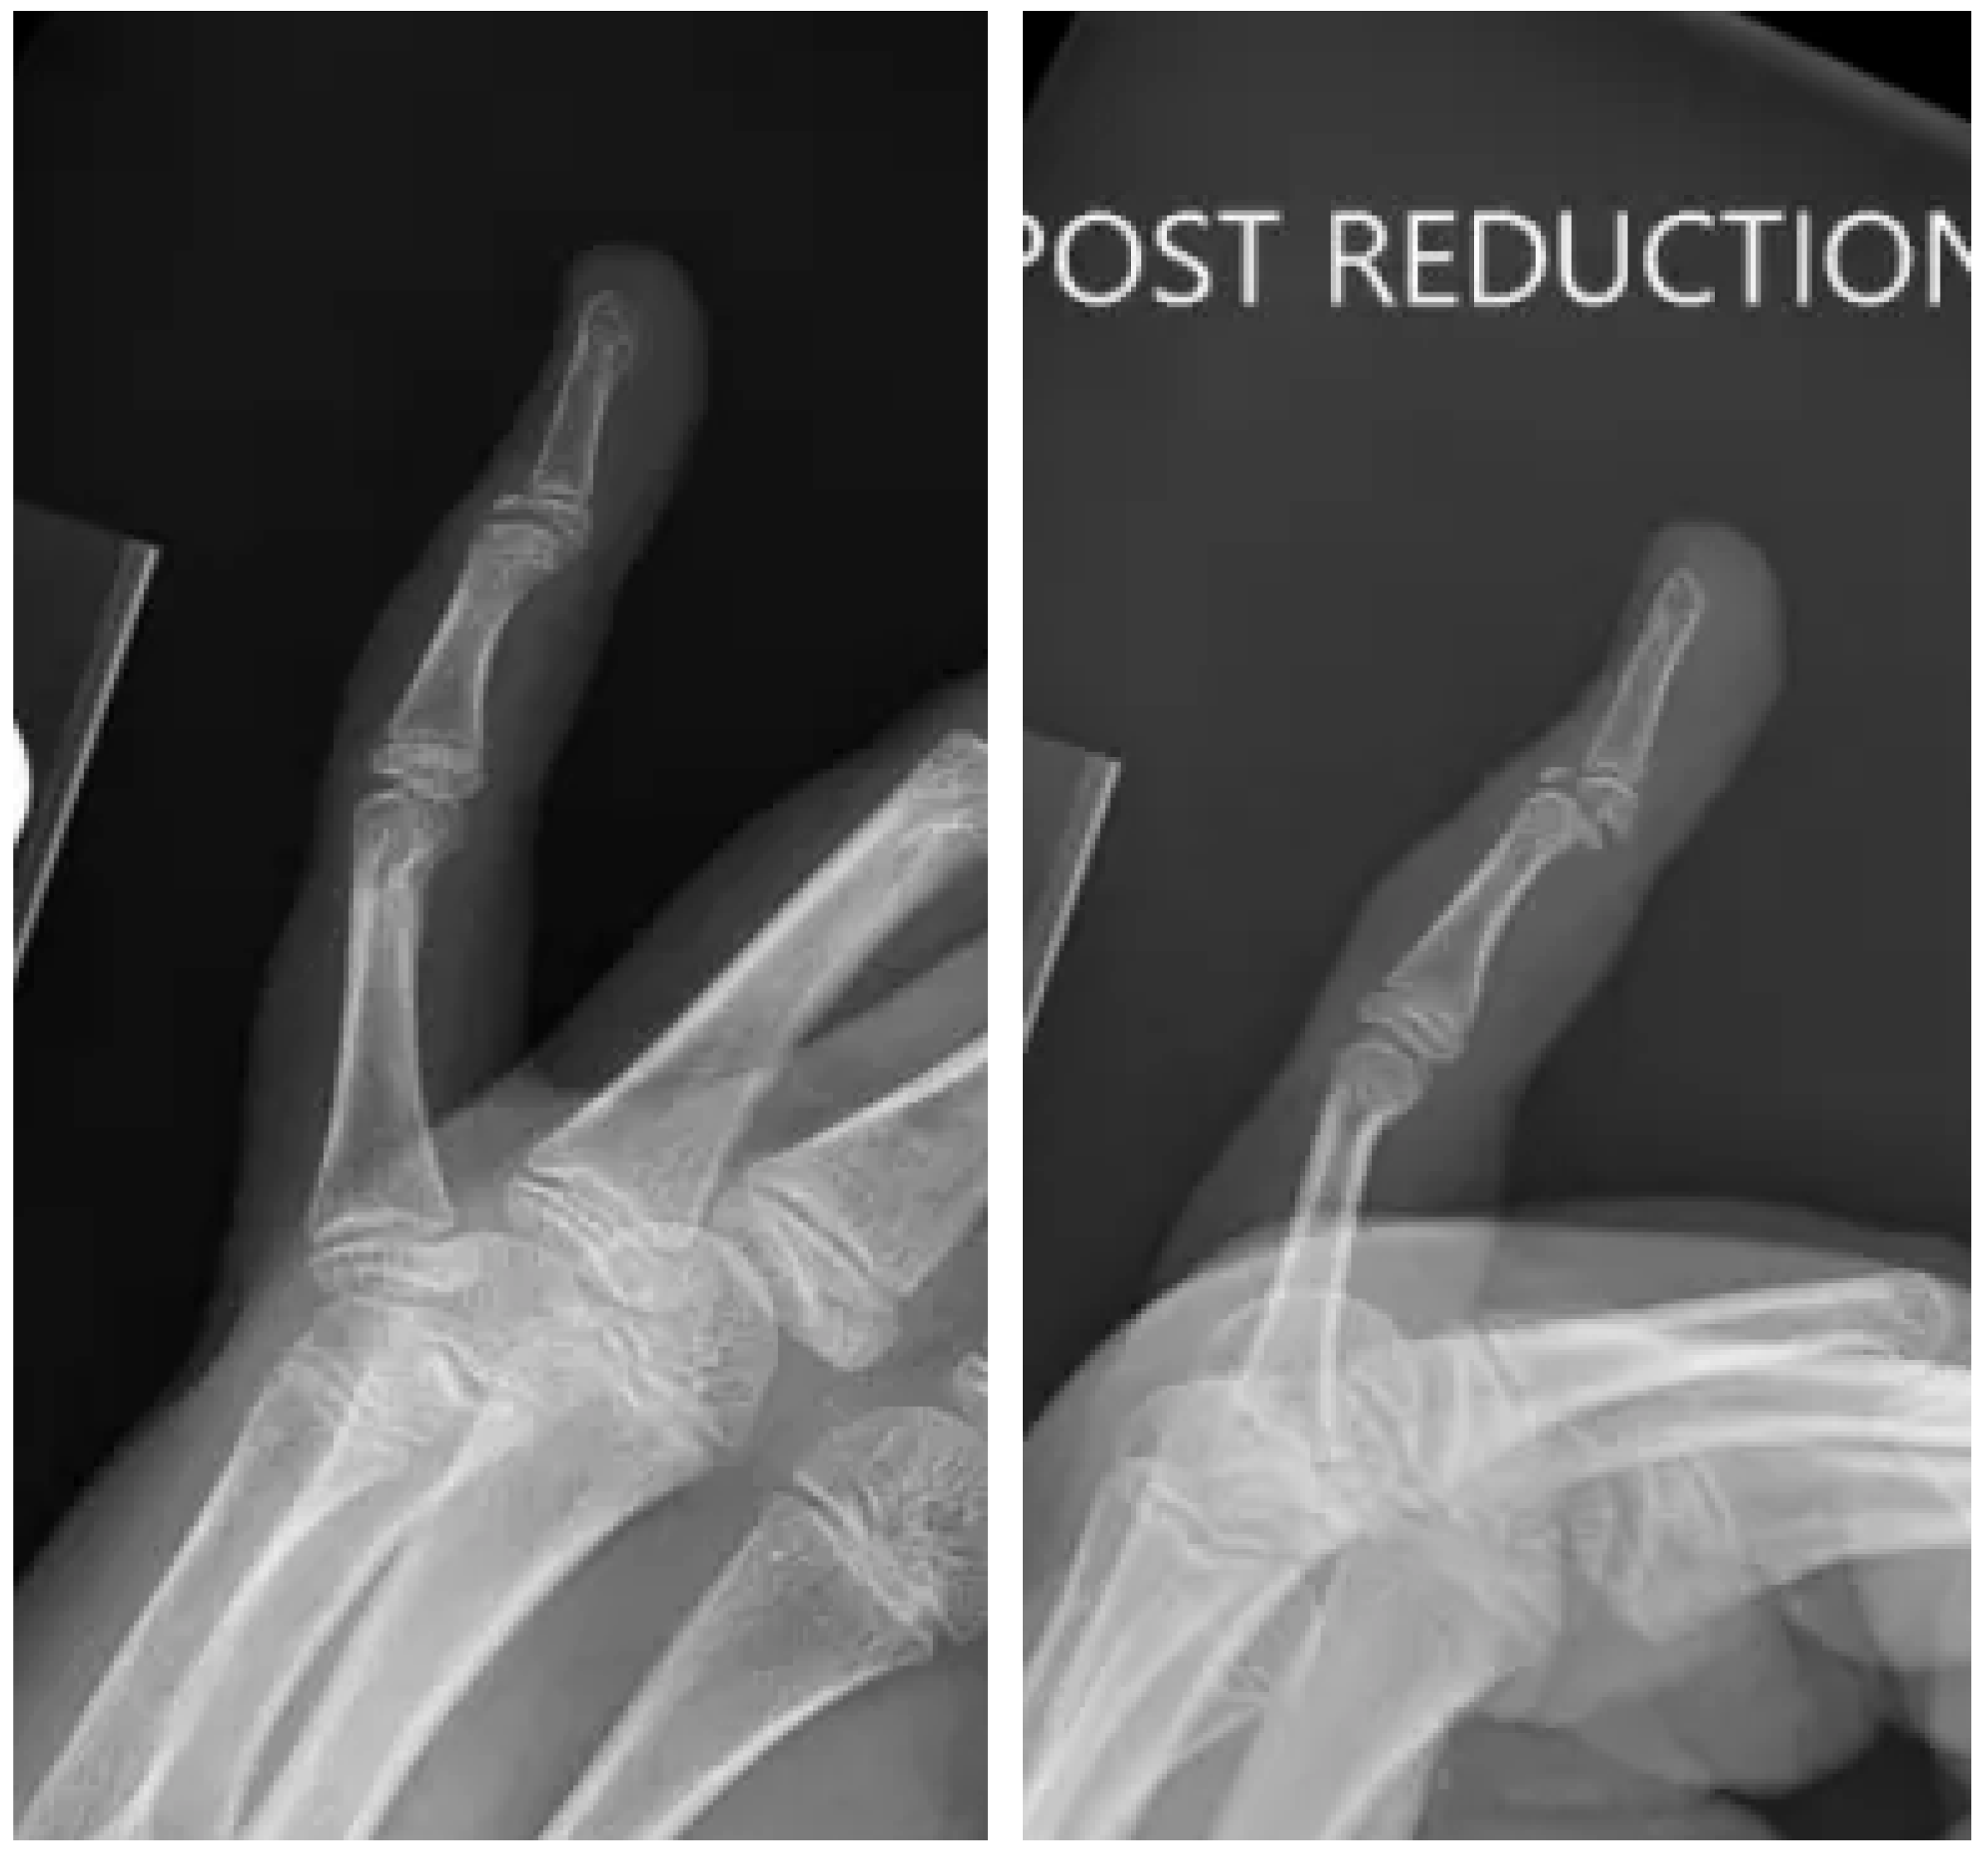

2. Case Presentation

2.1. Surgery